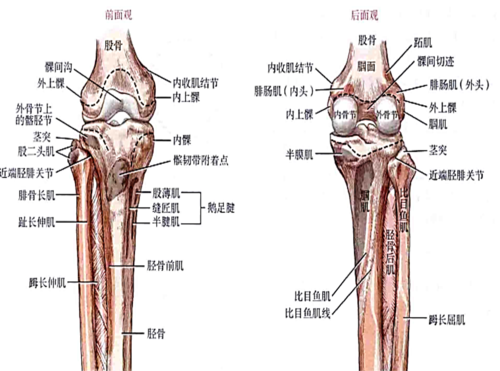

胫骨内侧髁

胫骨内侧髁,胫骨内髁

(八)胫骨 上端—内侧髁 外侧髁 胫骨粗隆 内侧髁 外侧髁 胫骨粗隆

髌骨与股骨的髌面相接,股骨的内,外侧髁分别与胫骨的内,外侧髁相对.

胫骨近侧端膨大,向两侧突出成为内侧踝与外侧髁. /p>

胫骨内侧髁解剖

胫骨内侧髁位置

胫骨内侧髁位置图